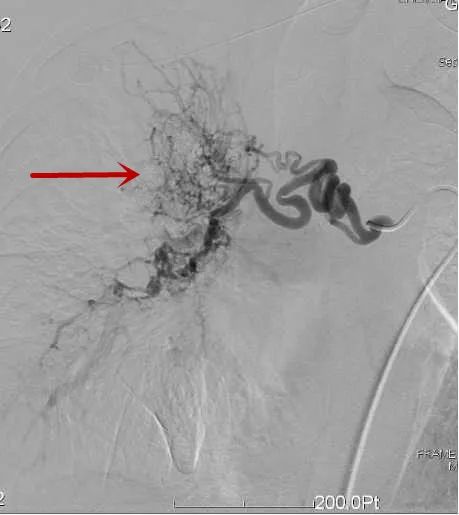

△造影找到出血動脈/找到出血責任動脈/精準栓塞后出血動脈已閉塞

肝癌破裂出血介入止血

△肝內腫瘤破裂出血/栓塞后造影示腫瘤出血已止住

大咯血介入治療

△術中見肝內血管片破裂出血/栓塞后肝出血動脈已閉塞

腎碎石后尿血介入治療

△找到出血動脈/進行栓塞止血/再次造影明確出血已止住